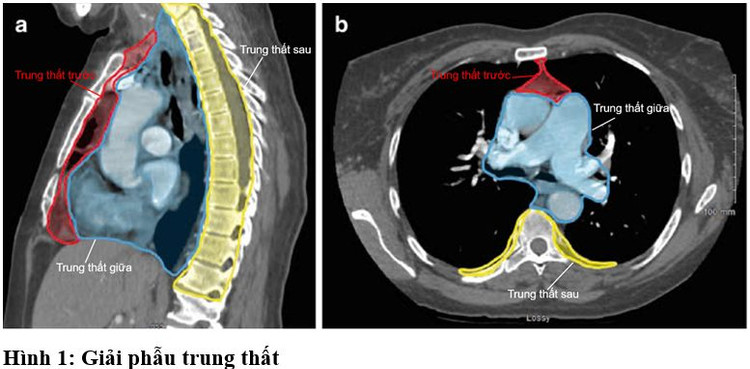

Trung thất là vùng trung tâm của ngực chứa nhiều cơ quan quan trọng như tim, thực quản, khí quản, mạch máu lớn, dây thần kinh, tuyến ức… Nó được bao bọc phía trước là xương ức và các sụn sườn, phía sau là các đốt sống ngực, 2 bên là màng phổi, mặt dưới là cơ hoành, phía trên là vùng nền cổ.

![]() |